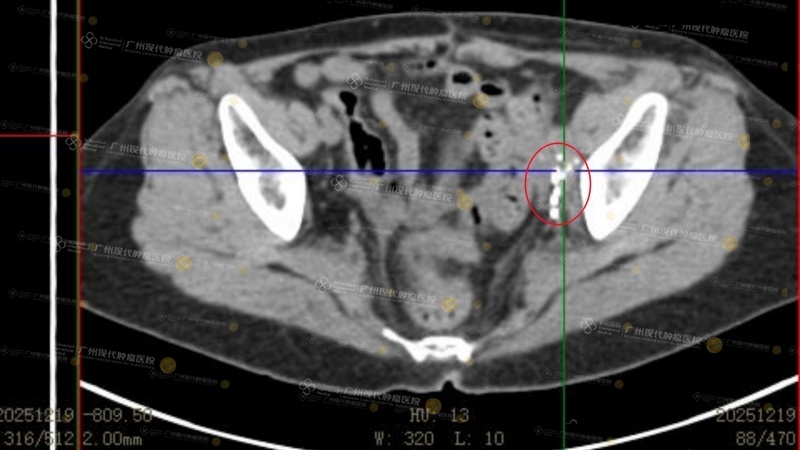

Hiệu quả thấy rõ ngay tức thì: sau lần điều trị đầu tiên kết thúc, cơn đau bụng đã hành hạ bà suốt thời gian dài liền biến mất. Sau lần điều trị thứ hai, tuần hoàn máu ở chân được phục hồi, tình trạng sưng chân trái giảm rõ rệt. “Điều này đã cho tôi niềm tin rất lớn,” Phù Ái Cầm hào hứng chia sẻ, “sau khi kết thúc lần điều trị thứ tư và chụp PET scan, thực sự có thể nhìn thấy khối u đã thu nhỏ rõ rệt.” Trải qua ba tháng điều trị, tính đến hiện tại, hạch lympho vùng chậu của Phù Ái Cầm về cơ bản đã mất hoạt tính hoàn toàn, khối u ở gan đã biến mất, đánh giá hiệu quả điều trị tổng thể có thể đạt PR.

(Sau 4 lần điều trị, kết quả tái khám ngày 19 tháng 12 năm 2025 cho thấy khối u về cơ bản đã mất hoạt tính hoàn toàn)